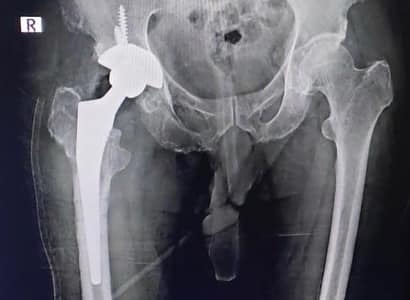

Management of a neck of femur fracture in a 61 year old often fails for various reasons, like in this gentleman operated in some remote district and showing no sign of union or improvement after 8 months as witnessesd in the first xray. Under such circumstances, total hip replacement is our go to procedure. With this surgery this person can now easily walk after suture removal on 14th day post surgery.